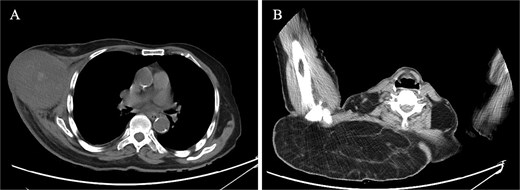

Laboratory investigations, including a complete blood count, liver function tests, kidney function tests, and electrolytes, were all within normal limits. Imaging studies provided more insight into the patient's condition. Breast ultrasound revealed a heterogeneous mass, inferior and lateral to the right breast, measuring 8.1 × 7.5 cm. The mass was semisolid and partially compressible, with internal cystic spaces and vascularity. Unenhanced computed tomography (CT) of the chest demonstrated a heterogeneous mass lesion in the right breast, measuring 8.0 × 8.7 cm, with hyperdensities and no calcifications, extending from the mid to anterior axillary line. Additionally, there was a large, fat-density lesion in the upper back, suggestive of a lipoma. There was no evidence of distant metastases (Fig. 2).

CT findings. (A) CT scan of right breast showing heterogeneous mass, measuring 8.0 × 8.7 cm, extending from the mid to the anterior axillary line. (B) CT scan of right upper back showing a large, fat-density mass, suggestive of lipoma.